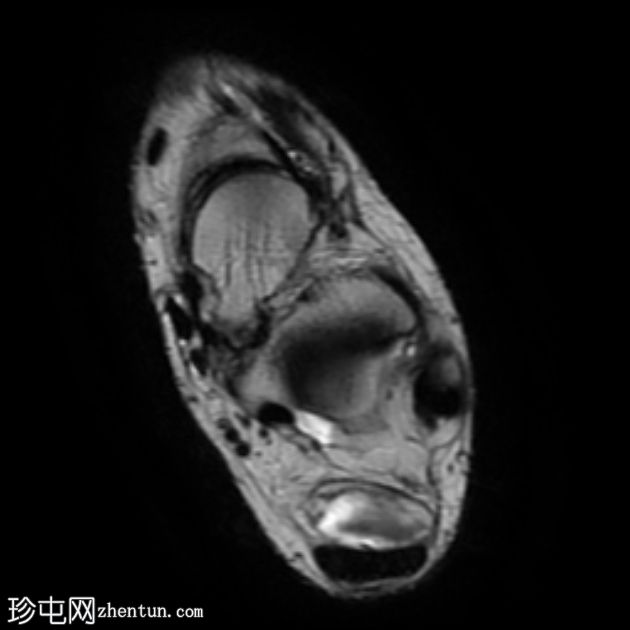

轴向

T2

跟腱插入

,伴有跟腱明显增厚,可诱发异常信号、跟腱后滑囊炎、跟骨后突及骨髓水肿信号。

Haglund综合征的检查结果令人印象深刻。

Haglund综合征是指以下三联征(Haglund三联征):

跟腱插入性病

跟腱后滑囊炎

Haglund畸形(即跟骨后上外生骨疣)